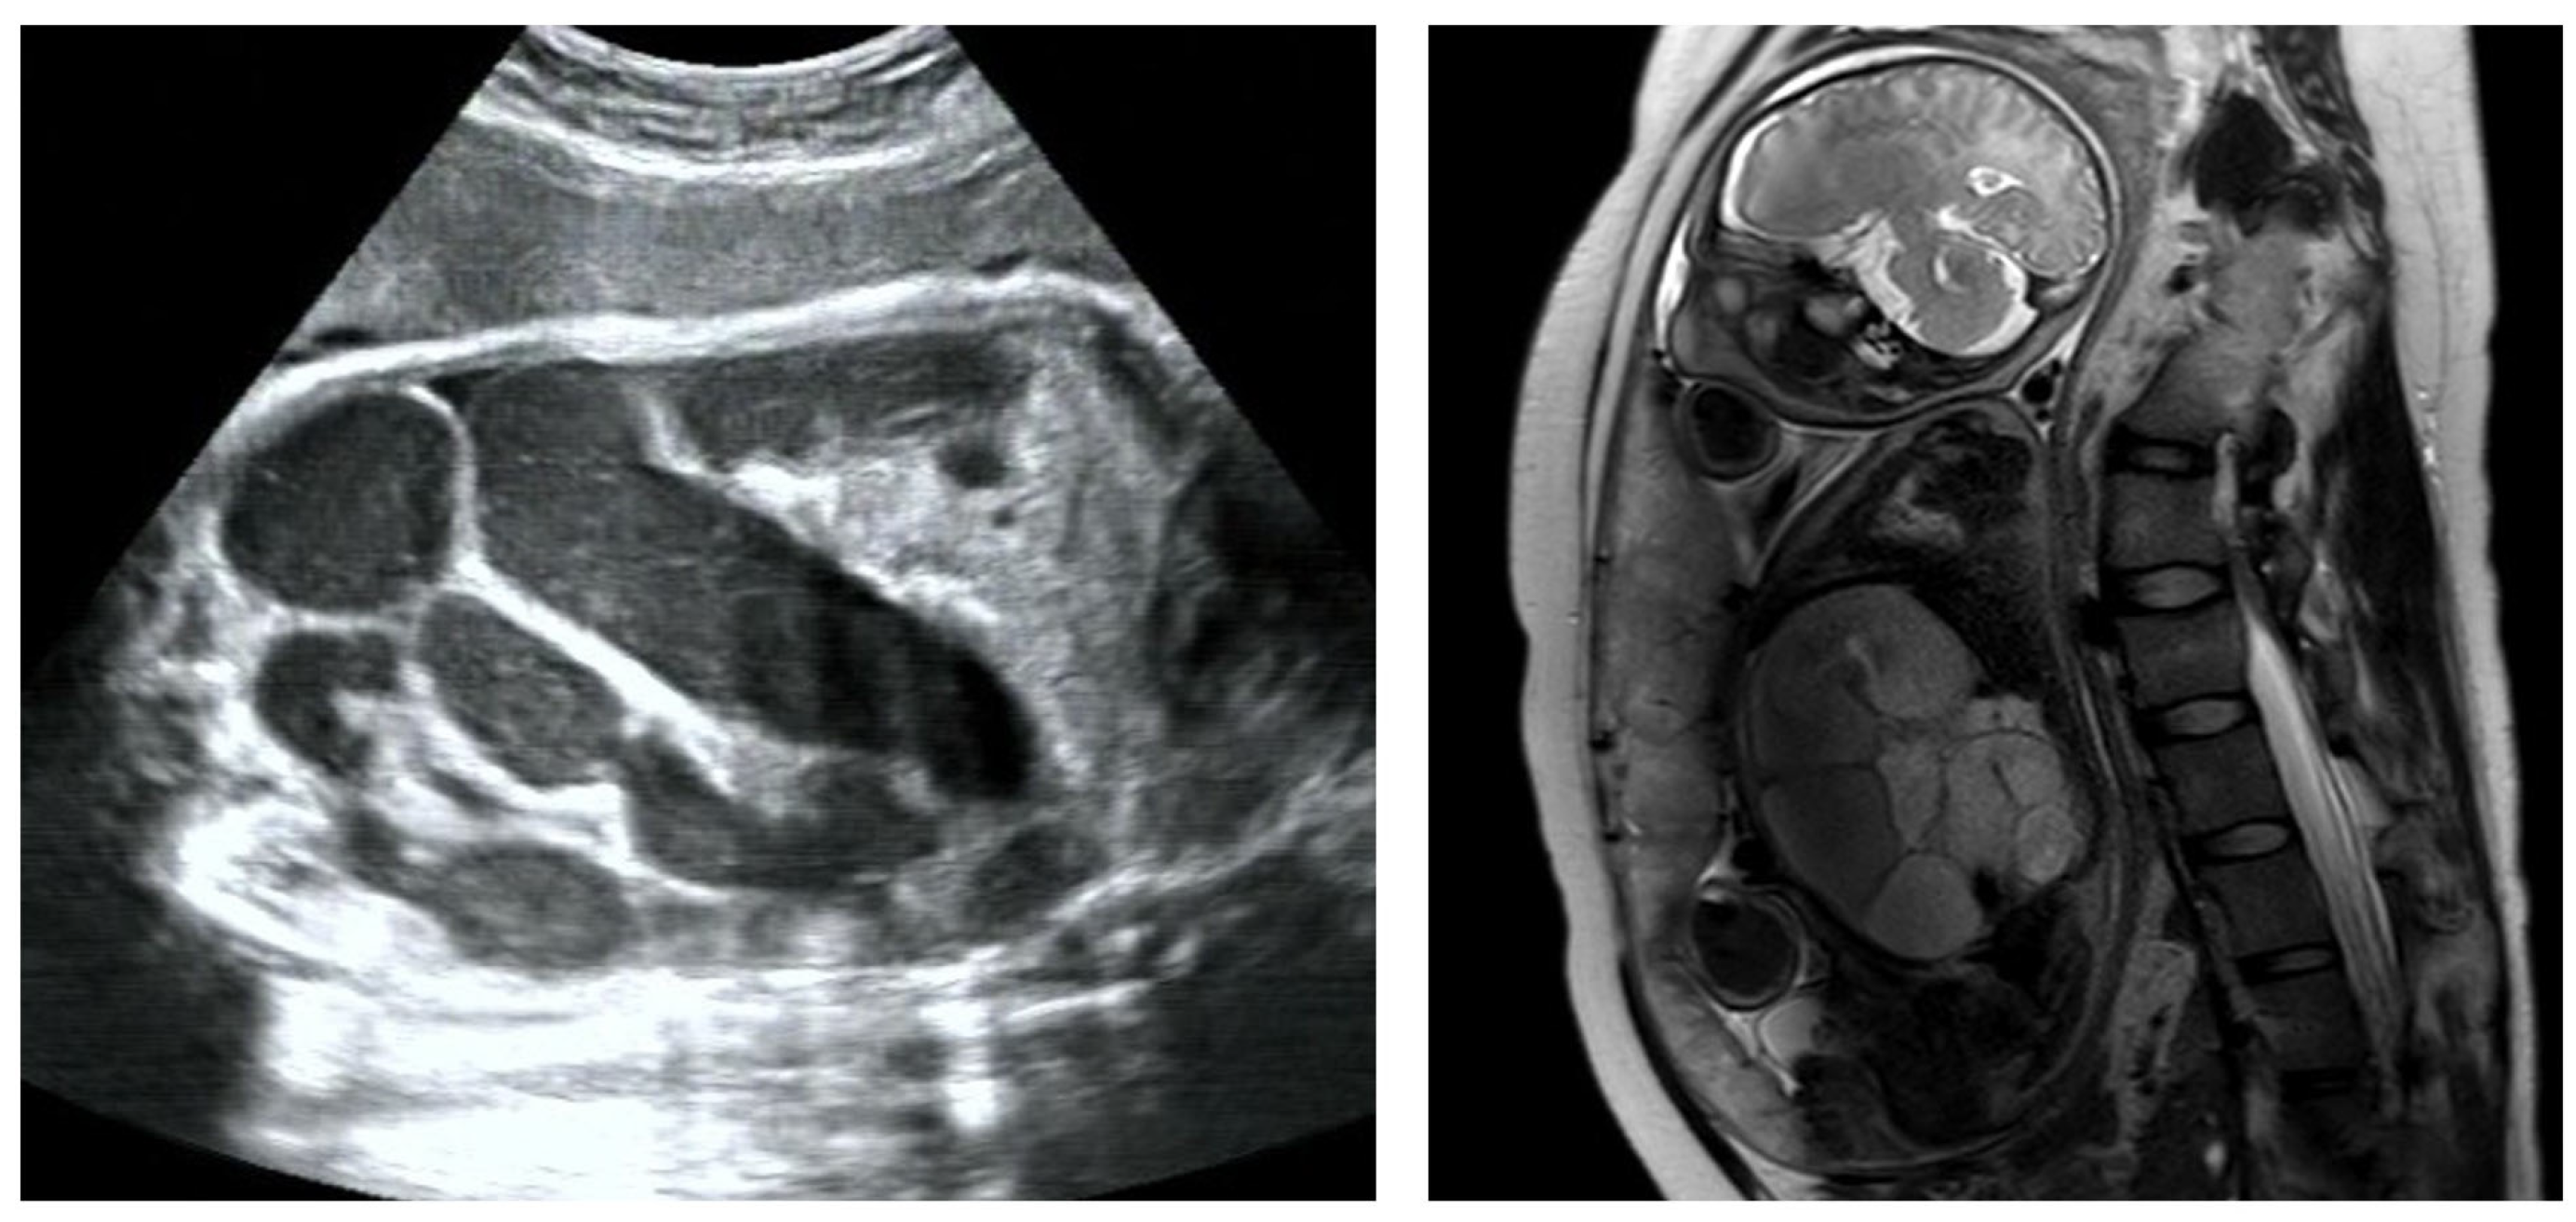

Based on fetal ultrasound and MRI assessments, lower digestive tract dilatation was observed in 72 fetuses. In these cases, dilated bowel appeared separately, with no connection with gastric bubble, indicating that the dilatated segment was in the jejunoileum or colon (Figure 2). The average GA at first time of diagnosis was 31.4 ± 5.1 weeks of gestation (range, 19+5–40+6 weeks).

Figure 2. Bowel dilation in ultrasound and MRI examination.